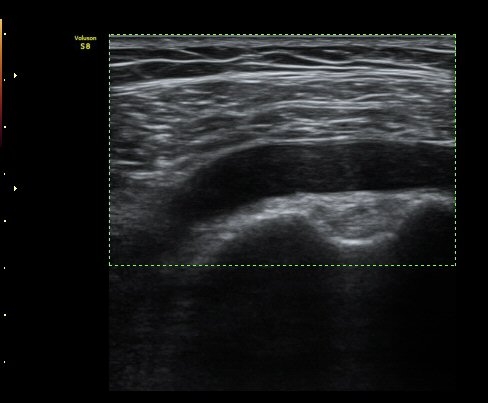

ÃÊÀ½ÆÄ °Ë»ç

¾î±ú À̵ιڱ٠Ⱦ´Ü¸é°Ë»ç¿¡¼­ ½ÉÇÑ Á¡¾×³¶³» ¼ö¾×Àú·ù°¡ °üÂûµÇÁö¸¸ ÆÄ¿öµµÇ÷¯

°Ë»ç¿¡¼­ Ç÷·ùÁõ°¡´Â °üÂûµÇÁö ¾Ê´Â´Ù(±×¸² 1, 2).   À̵ιڱ٠¾Æ·¡ Ⱦ´Ü¸é°Ë»ç¿¡¼­